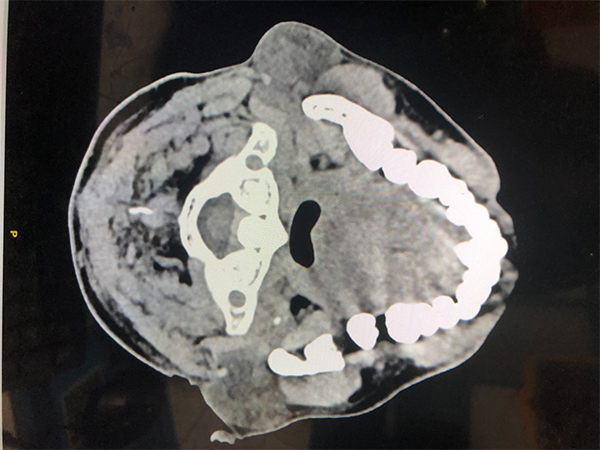

患者為中年男性,因“右側(cè)耳后腫物1年”入院。患者自述1年來(lái)發(fā)現(xiàn)右側(cè)耳后腫物漸進(jìn)性增長(zhǎng),抗炎治療無(wú)效,現(xiàn)影響面容遂來(lái)就診。

李家鋒主任醫(yī)師團(tuán)隊(duì)成員在術(shù)前對(duì)患者病情進(jìn)行了全面評(píng)估,通過(guò)詳細(xì)的影像學(xué)檢查,制定了個(gè)性化的手術(shù)方案。